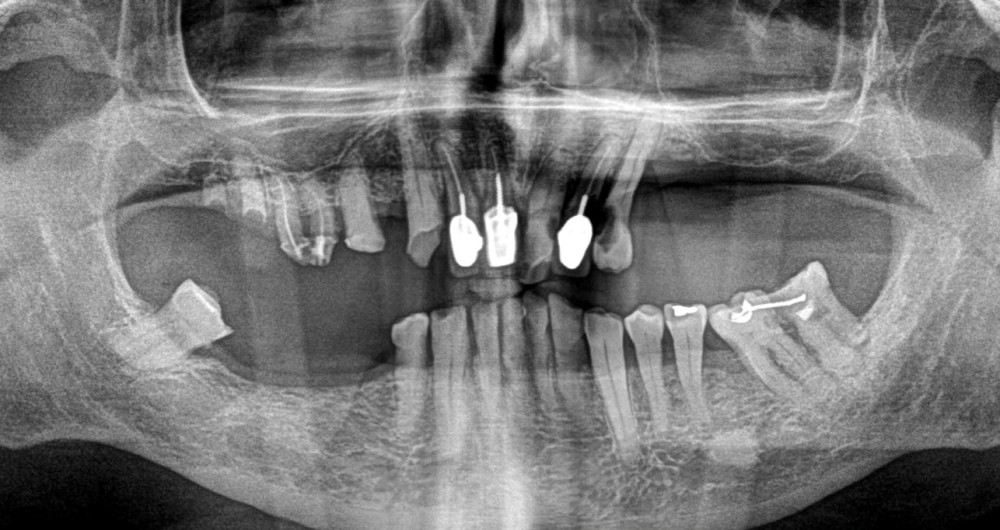

Un patient de 84 ans, en bon état de santé générale, consulte pour la perte de trois couronnes solidarisées métalliques 17, 16 et 15 qui permettaient la rétention d’une PAP à châssis métallique (fig. 1 à 5).

L’examen clinique permet de mettre en exergue, au maxillaire :

– 17, 16 sont à l’état de racines, 15 est déjà préparée et ne présente aucune symptomatologie pulpaire ;

– 13 est intacte ;

– 12 est couronnée et présente une mobilité importante et un épaississement ligamentaire ;

– 11 est couronnée ;

– carie radiculaire importante à la 21 ;

– 22 est couronnée et présente également une carie radiculaire ;

– 13 est très cariée et présente une alvéolyse dépassant le tiers apical de la racine.

À la mandibule, nous notons que :

– les dents 45, 46, et 47 sont absentes ;

– la dent 37 est liée à 36 par un jonc retenu dans un composite et présente une image apicale et une alvéolyse distale dépassant le tiers de la racine. L’édentement n’a jamais été compensé.

Le patient est fumeur depuis plusieurs dizaines d’années. Nous relevons plusieurs…